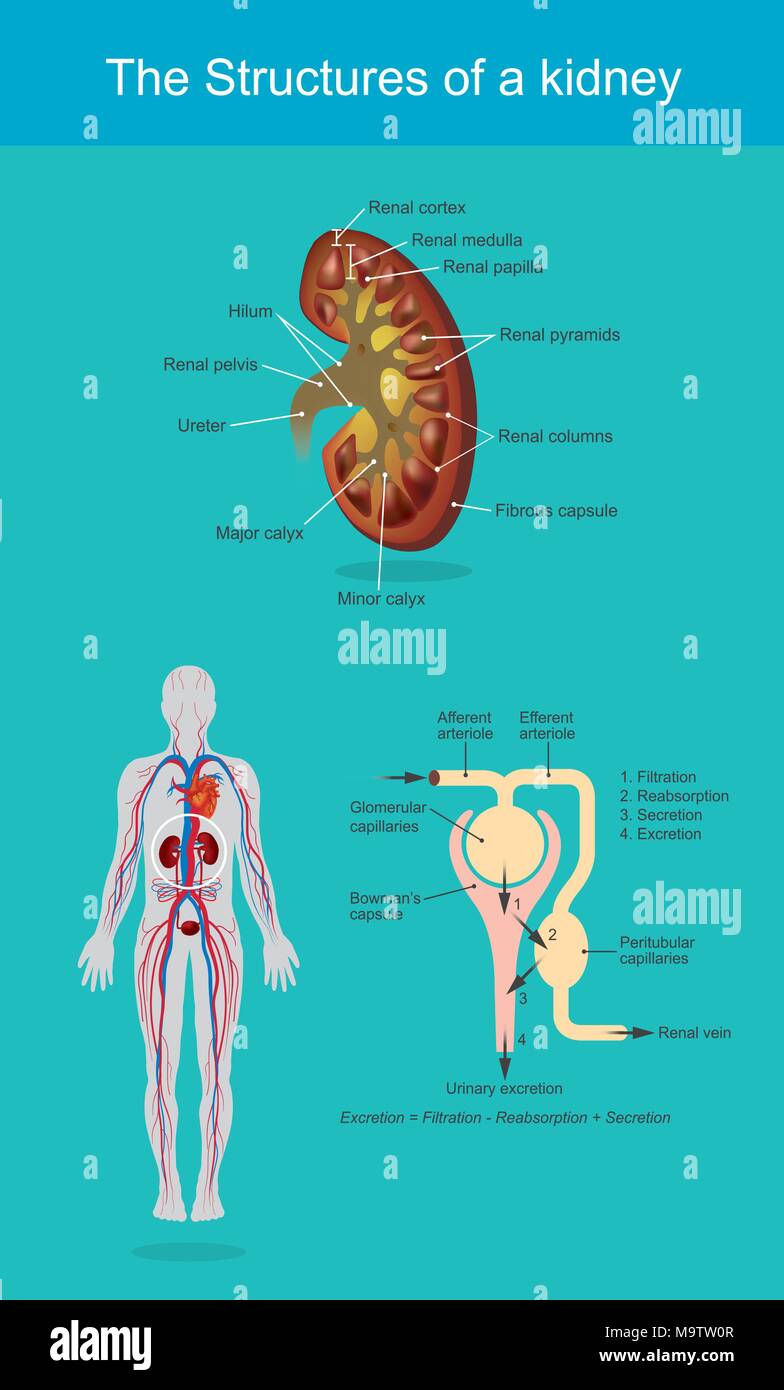

I reni sono organi a forma di fagiolo che servono alcuni essenziali funzioni regolatorie nei vertebrati. Illustrazione Vettorialehttps://www.alamy.it/image-license-details/?v=1https://www.alamy.it/i-reni-sono-organi-a-forma-di-fagiolo-che-servono-alcuni-essenziali-funzioni-regolatorie-nei-vertebrati-image178182055.html

I reni sono organi a forma di fagiolo che servono alcuni essenziali funzioni regolatorie nei vertebrati. Illustrazione Vettorialehttps://www.alamy.it/image-license-details/?v=1https://www.alamy.it/i-reni-sono-organi-a-forma-di-fagiolo-che-servono-alcuni-essenziali-funzioni-regolatorie-nei-vertebrati-image178182055.htmlRFM9TW0R–I reni sono organi a forma di fagiolo che servono alcuni essenziali funzioni regolatorie nei vertebrati.